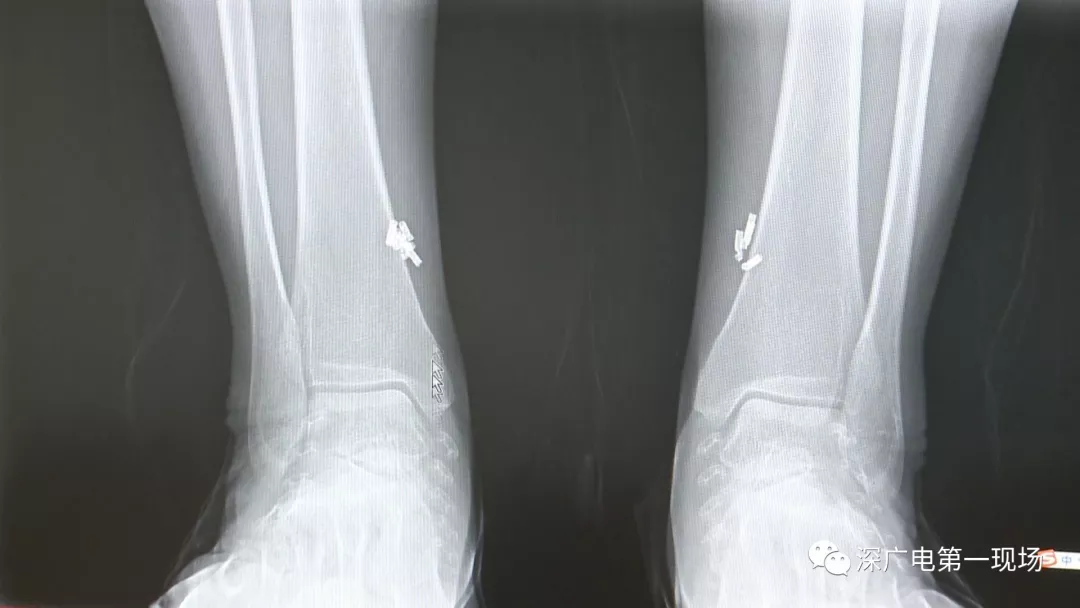

深圳一女子全身被植入彈簧圈,數(shù)量多到驚人!竟是為治這病…

出于保護(hù)患者,我們沒有直接采訪,但是通過(guò)醫(yī)生的介紹,記者了解到,病人是個(gè)36歲的女性,2歲開始就有癲癇病史,而且藥物治療也并不見效。

多方打聽之后,在山東某診所用全身埋彈簧圈的方式治療癲癇。陶主任介紹,這樣的方式想要治愈,那幾率也等同于撞大運(yùn)?。?/p>